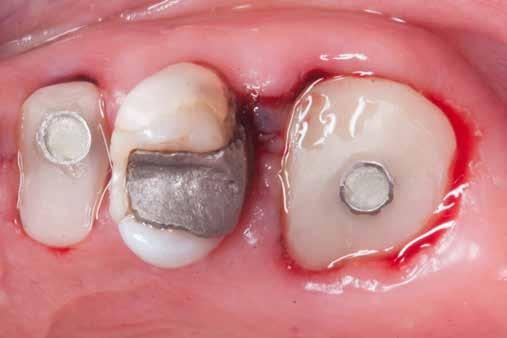

A mindennapi gyakorlatban gyakran találkozunk súlyos fogszuvasodással. A fogorvosnak mindig kihívást jelent a döntés, hogy kihúzzuk és implantátummal pótoljuk, vagy megmentjük a fogat, de kétséges a hosszú távú prognózis. Számos cikkből tudjuk, mint például Seltzer és Kim (Comparison of Long term survival of implant and endodontically treated teeth J Dent Res 93(1):19-26, 2014) cikke, hogy a fogak viszszanyerése jobb megoldás, különösen a fiatalabb betegeknél. A kirakós hiányzó kulcsa az általános fogorvos számára gyakran a maradó fogazat jó biomechanikai értékelése. Az endodontikusan kezelt fogak kudarcainak többsége valójában mechanikai hibákhoz, például repedéshez és töréshez kapcsolódik. A maradó fogszerkezet gondos biomechanikai értékelése, valamint a mechanikai teljesítményt javító technikákra való összpontosítás a legfontosabb a hosszú távú eredmény keresésében. A szerző praxisában a vertikális pre-

parálás és a minimális megközelítés kombinációja, valamint az ortodontikus extrúzió alkalmazása a restauratív fogászatban megváltoztatja a helyzetet, amint azt a következő eset is mutatja.

Az implantológia térhódítása után a restauratív/protetikai fogászatban a léc magasabbra került. A fogászati implantátumokkal való sikeresebb „versenyzéshez” a fogorvosoknak sokkal jobban kell összpontosítaniuk a fogak biomechanikai helyzetének értékelésére és javítására. A biomechanika mély megértése és a fogak teherbíró képességét javító technika alkalmazása a legfontosabb a hosszú távú siker érdekében.

Egy 35 éves kaukázusi férfi páciens az 1.4-es fog (felső első premoláris) törése miatt kereste fel rendelőnket, a törés ferde volt. A sérült fogak helyreállítása során az egyik legfontosabb lépés a megmaradt fogazat biomechanikai értékelése . Egy hiba ebben a fázisban káros a hosszú távú eredményre . A legtöbb repedést például a fogüregek helyreállító fogászathoz való helytelen előkészítése okozza. Ugyanígy a fennmaradó szerkezet helytelen értékelése idővel mechanikai okokból bekövetkező meghibásodáshoz vezethet.

4. ábra: A fogszerkezet helyreállítása és a fogrestaurációs komplexum ellenálló képességének javítása érdekében ortodontikus extrúziót végeztek a szomszédos fogakra ragasztott drót és egy egyszerű rugalmas ligatúra segítségével.

10. ábra: A cirkónium-dioxid korona cementálása üveg-ionomer cementtel . Ezzel a megközelítéssel nyilvánvaló, hogy a ferrule menynyisége a szomszédos fogakra gyakorolt bármilyen komplikáció nélkül nyert. A parodontális apparátus valójában érintetlen. Nincsenek fekete háromszögek, nincs a szomszédos fogak gyökérkitettségének kockázata. Már a szülés napján megvan a papilla, amely kitölti az intraproximális tereket. A nyert ferrule mennyisége hatalmas. A bukkális falon könnyen felismerhetjük, hogy az egész fal már szilárd fogazati struktúrán van, a palatális falon pedig az ajánlott 1-1,5 mm-nél jóval több. A függőleges preparálással szintén könnyen meg tudjuk tartani a visszanyert fogszerkezet mennyiségét , különösen a pericervikális dentin területén, ami a legfontosabb a hosszú távú eredmény szempontjából.